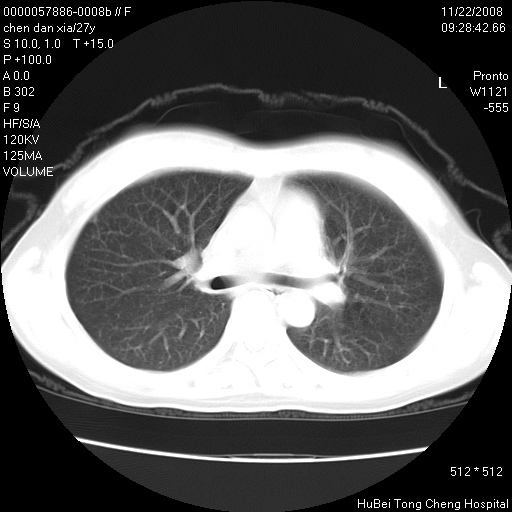

标题: CT16752:F,27Y。发热咳嗽20余天,伴盗汗。 [打印本页]

标题: CT16752:F,27Y。发热咳嗽20余天,伴盗汗。

考虑双肺粟粒性肺tb,右侧胸膜增厚.

气管前腔静脉后淋巴结肿大 右肺门纹理模糊

淋巴结核?

右下肺见片絮状影,两肺野内分布不均的小结节影,结核并肺内播散可能性大,建议结合实验室检查 .

右下肺纹理模糊;纵隔可见肿大淋巴节;右心缘旁结节,边缘光滑,纵隔窗病变范围较肺窗明显小,首先考虑右下肺结核,不排外淋巴瘤

双肺纹影普多,部分呈网状,支炎或淋巴管炎?

纵隔内淋结肿

局部胸膜增厚

下肺结节,结节内钙化,肺门纵隔淋巴肿大 结核可能性大

似有粟米状结节。考虑粟粒型肺结核?

1)考虑两肺感染性病变。2)纵隔淋巴结肿大。